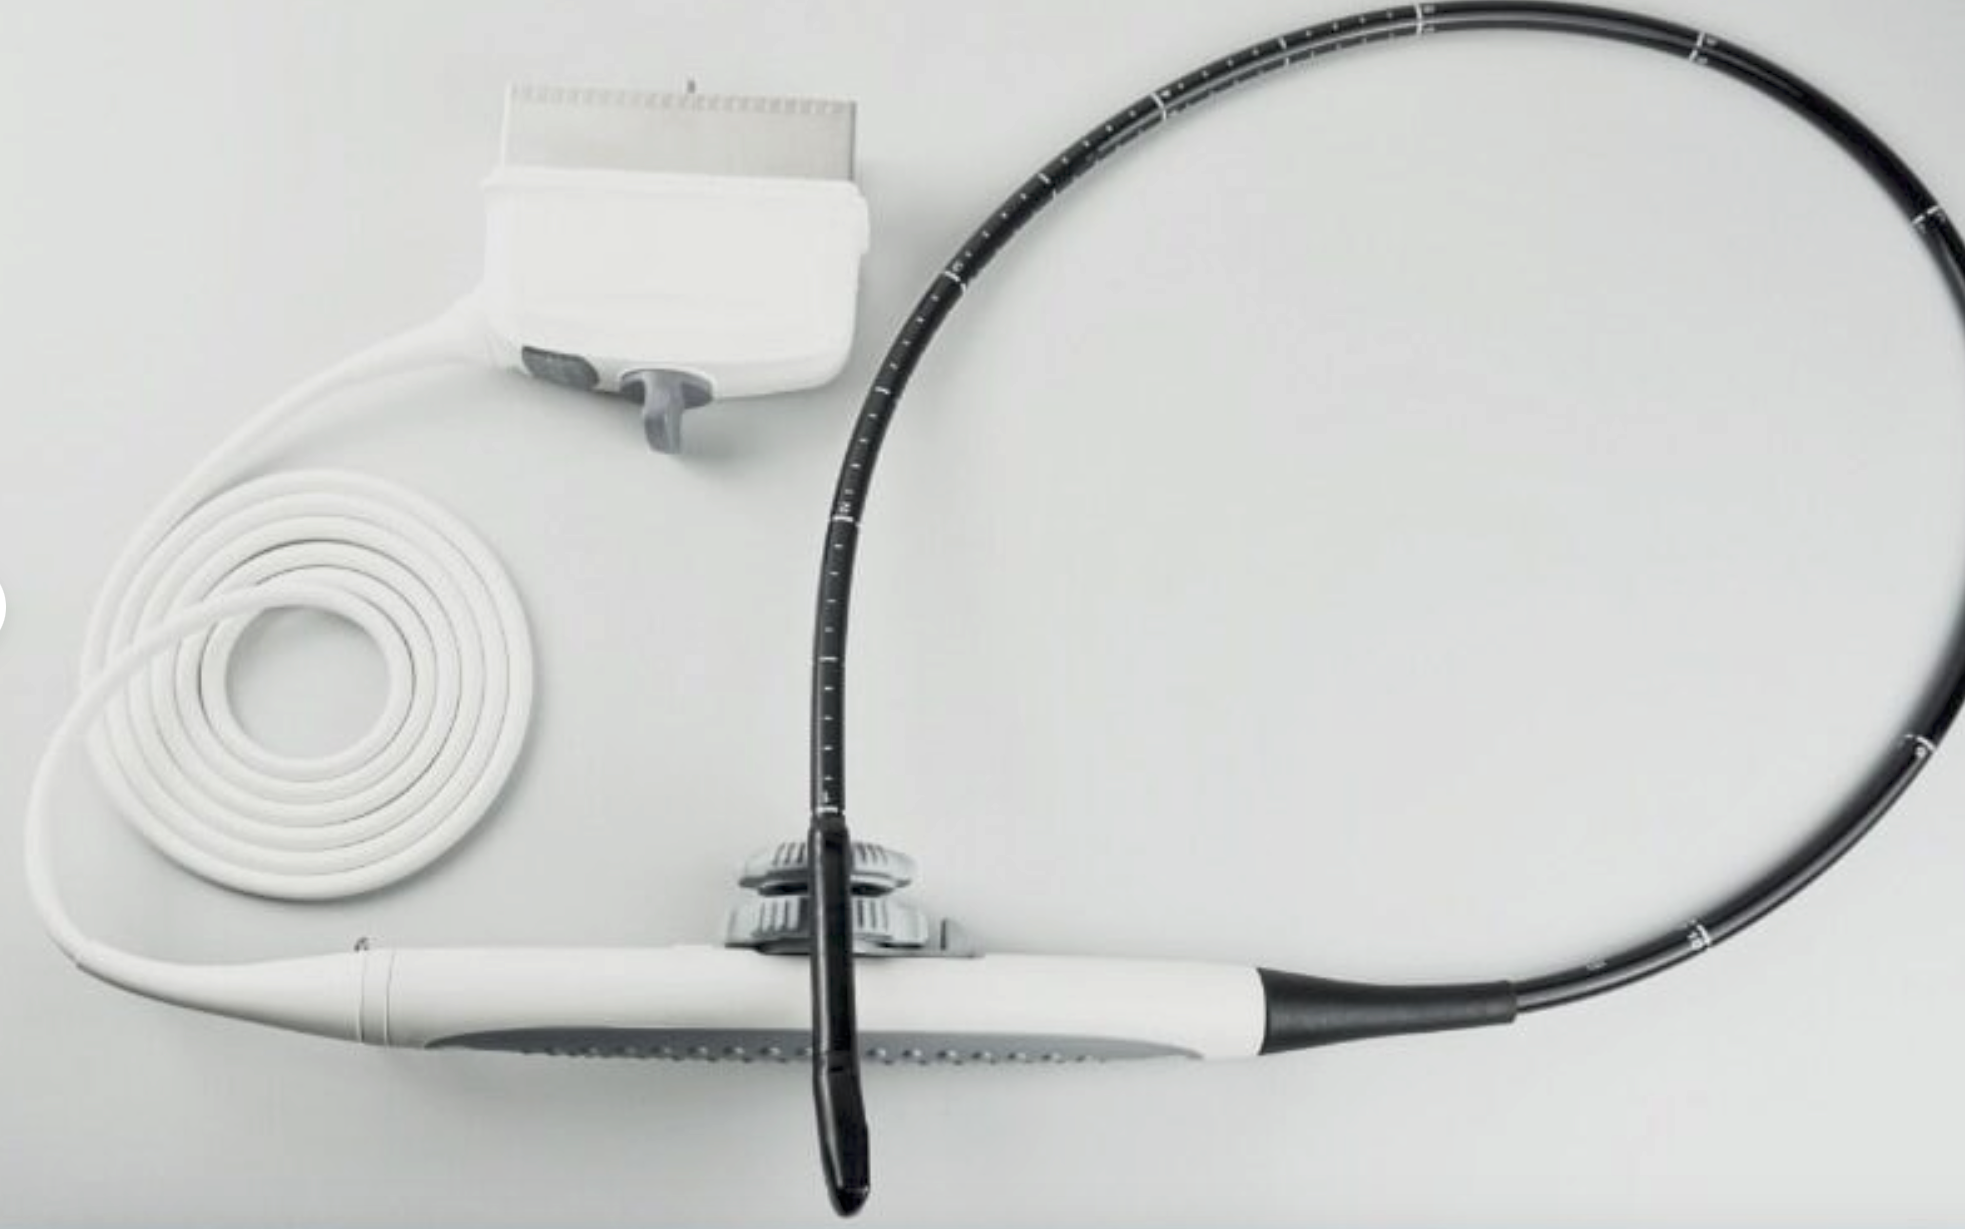

SONOSITE TITAN PORTABLE ULTRASOUND (w242)

Sale price$ 6,888.00